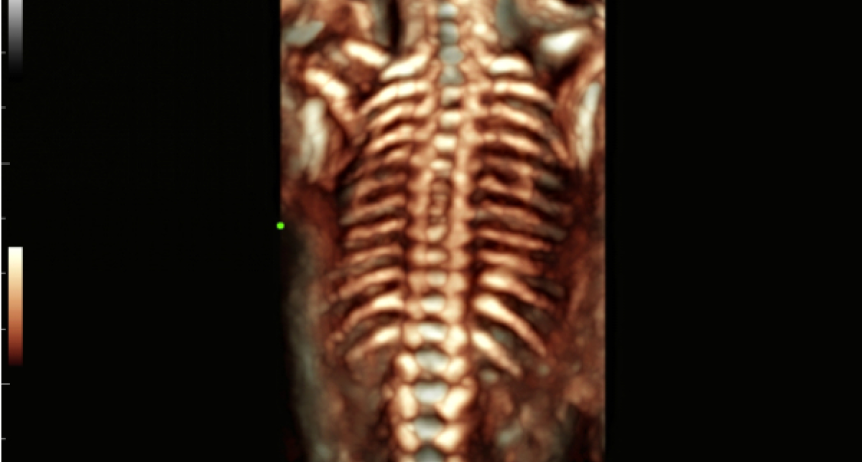

COLUMNA VERTEBRAL FETAL 3D